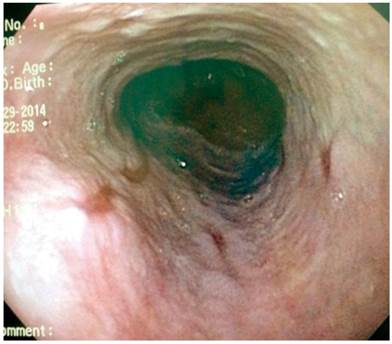

La paciente presenta un antecedente relevante de válvula ventrículo-atrial de Hakim desde los 20 años, por causa de un pseudotumor cerebral. Entre tanto, en 2010 se encontró una várice esofágica superior, mediante una esofagogastroduodenoscopia (EGD) (Figura 1). A partir de este examen le fue descartada una patología venosa obstructiva, luego del resultado anterior, con persistencia de la várice esofágica superior y sin estigmas de sangrado o de riesgo en 2016.

Paciente AMDA: mujer de 73 años con diagnóstico clínico de RGE, con antecedente de EPOC por exposición al humo de leña, uso permanente de inhaladores y oxígeno suplementario en casa. En el momento del examen físico se presenta con obesidad, cianosis de piel y mucosas y abotagamiento (Figura 2). En la EGD, se encontraron várices en los 6 primeros centímetros del esófago (Figura 3) con ausencia distal de estas (Figura 4), sin estigmas de sangrado o de riesgo y gastritis crónica superficial.